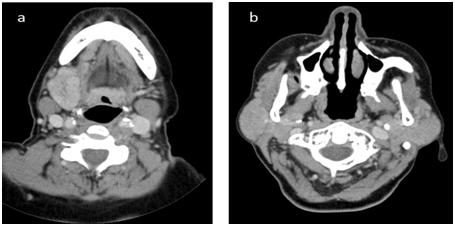

A 60-year-old woman was admitted to our clinic with the complaint of a slow-growing mass in the left submandibular region for 4 months. She had no history of drying eyes or mouth. She was with normal general health and no other personal history of disease. Physical examination revealed a very firm, slightly tender, 4×3 cm sized left submandibular mass. Ultrasonography showed diffuse enlargement with impaired parenchymal structure in the left submandibular gland. But there was no sign of sialolithiasis. No other masses or adenopathy were noted in the head and neck in physical examination and ultrasonography. Flexible endoscopic examination of the nasopharynx, hypopharynx, larynx was normal. Fine needle aspiration cytology showed a non-specific inflammation. Routine laboratory tests including full blood count, white cell count, liver function tests, erythrocite sedimentation rate were within normal range. Left submandibular gland excision was performed under general anesthesia. Light microscopic examination of tissue stained with he­matoxylin and eosin revealed remarkable fibrosis,  accompanied by the inflammatory infiltrate and lymphoid follicules (Figure 1A). Acinar atrophy, concentric periductal sclerosis(“onion-skin’’ appearance), and ductal ectasy were also observed (Figure 1b). But there were no neoplastic features. All these findings were consistent with chronic sclerosan sialadenitis. The patient recovered well after operation. But she presented with a prominent right submandibular mass and mild bilateral symmetric parotid swelling three months later (Figures 2A & 2B). Right submandibular mass had the same clinical features of the left. Computed tomography of the neck with contrast was also performed. It showed diffuse enlargement of the right submandibular and bilateral parotid gland which enhance moderately (Figure 3). The patient underwent operation again and right submandibular gland was surgically removed. Histological features of the excised right submandibular gland same as the left submandibular gland. Specimens of the bilateral submandibular glands displayed the histopathologic features of the chronic sclerosing sialadenitis. Bilateral submandibular gland specimens predominantly showed the stage 2 KT according to Seifert’s histopathologic classification (Table 1). We also performed immunohistochemical staining. Inflammatory infiltrate were composed of CD4+ T cells (helper T cell) and CD8+ T cells (cytotoxic T lymphocyte) in periductal area (Figures 4A&4B). A large number of CD 138+ cells(plasma cell) were also observed in interfolliculer area (Figure 4c). Lymphoid follicules predominantly consisted CD 20+ cells (B lymphocyte) in the germinal center (Figure 4D). Patient was also positive for anti-nuclear antibody(ANA) in blood. These findings indicated that it may be an immune-mediated process and the patient was referred to an immunologist for excluding the autoimmune diseases. Other autoimmun antibodies were not detected. IgG and IgG4 level that might be elevated in IgG4-related systemic sclerosing disease were also normal range. Immunologist reported to have no evidence of otoimmun diseases in the patient because there was no sign of autoimmun disorder except the positive antinuclear antibody that considered as non-spesific. The patient was followed for 6 months without further therapy. No other neck masses detected in this period except bilateral mild parotid swelling. Patient did not mentioned dry mouth or any other symptom after surgery.

Figure 3 Axial CT scan showing the enlargement of the right submandibular gland (a) and bilateral parotid glands (b).